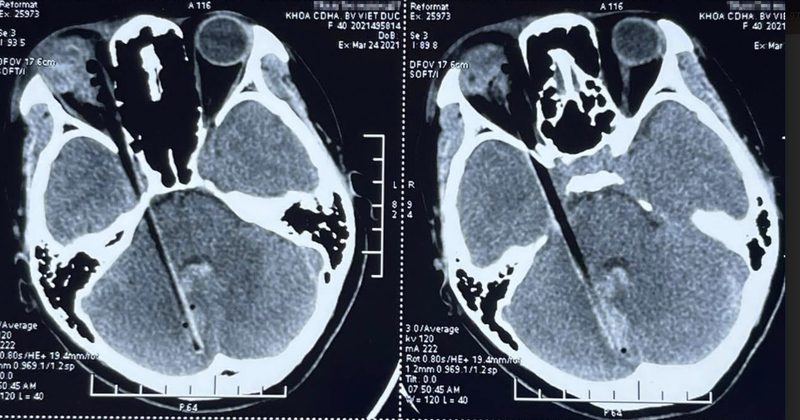

Hình ảnh dị vật đâm xuyên qua hốc mắt, vào sọ não của bệnh nhân (Ảnh - BVCC) |

Tại Bệnh viện Hữu nghị Việt Đức, các bác sĩ đã khám và chụp chiếu phát hiện hốc mắt của chị H. có dị vật là một mảnh gỗ dài, cắm vào thành trong hốc mắt. Mảnh gỗ này đã đi qua sát vùng xoang hang đến tận hố sọ sau rồi cắm vào tiểu não phải, sát thân não khiến bệnh nhân bị tổn thương, chảy máu.

Sau nhiều giờ căng thẳng, TS. Lê Hồng Nhân cùng nhóm phẫu thuật viên thần kinh đã lấy được mảnh gỗ dài thuôn nhọn ở đầu dài gần 12cm, dày 0,5cm cắm thành vào thành xương sọ của bệnh nhân.